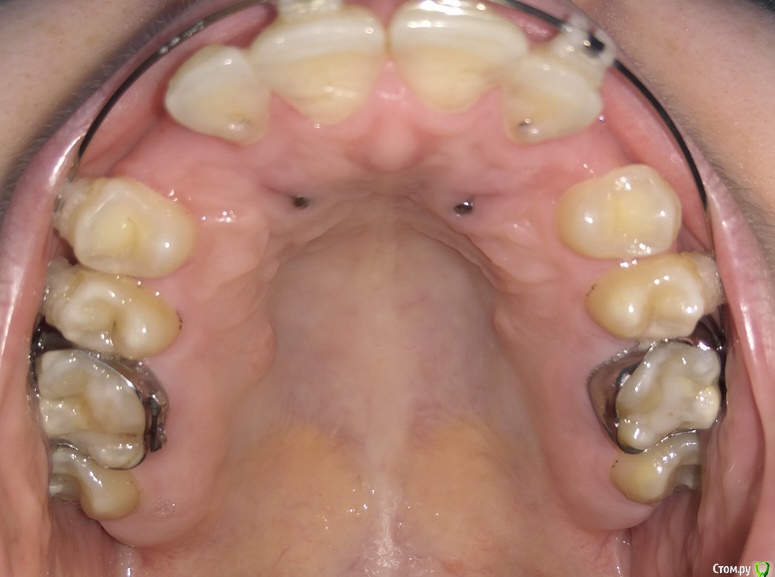

Добрый день. Уважаемые специалисты, прошу совета, БС была установлена в 2015 году, тогда же удалены молочные клыки, ортодонт сказал, что можно вытянуть, но как оказалось не все это могут сделать. Был сделан доступ к постоянным клыкам с небной стороны, приклеены кнопки, установлены лигатуры в области первых премоляров. В 2015-2016 была беременность. Примерно в феврале 2017 лигатуры были заменены на микроимплантаты в области первого моляра с небной стороны и установлены металлические лигатуры. В итоге - движение не наблюдается. Вопрос - можно ли еще пробовать их вытянуть или же делать радикально - удаление и имплантация, или после удаления можно сместить премоляры и моляры вперед?